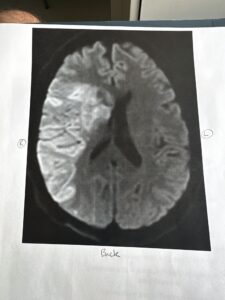

Within hours, Brandon was airlifted to UC Davis Medical Center, where doctors removed a blood clot and performed a large craniotomy due to dangerous swelling. Part of his skull was removed and stored while his brain recovered.

removed

a three millimeter blood clot from my main artery on the right side. But then the swelling was so bad because I had been bleeding into my brain for 12 hours overnight that they had to go ahead and do ⁓ a, what do you call it? The craniotomy. Yeah, craniotomy. And so they took this whole side. It was a big craniotomy.

They took this whole side, everything to the center of my forehead, above my eye, down to just above my ear, front to back. ⁓ They took that whole section of my skull out, put it in the freezer so that my brain had room. then I spent 10 days in intensive care recovering from that. And then they moved me to a rehab hospital where I spent four weeks.